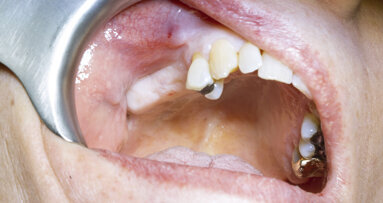

A 72-year-old patient in good general health presented with partial edentulism in the maxillary posterior region. The main goal was to achieve a rapid fixed prosthetic rehabilitation. After clinical and radiographic (2D and 3D) analysis, it was decided to proceed with a screw-retained bridge on implants, using multi-unit abutment connections to compensate for angulation and z-axis discrepancies. After guided surgery to place two internal hexagonal/conical connection implants, osseointegration time was allowed before prosthetic loading. The patient was informed that the entire prosthetic treatment would be completed on one day, since there would be no need for an external laboratory.

Intra-oral scanning After postoperative healing of the implants, multi-unit abutments and ProCam scan bodies were placed over the implants, and data was acquired with the Medit i700 wireless intra-oral scanner (Figs. 2a & b). The use of the intra-oral scanner allowed us to avoid physical impressions, thereby reducing patient discomfort. It also allowed for the capture of a detailed and accurate digital representation of the implant connections and enabled real-time evaluation of the scan quality.

Figs. 2a & b:: Intra-oral scanning using ProCam scan bodies.